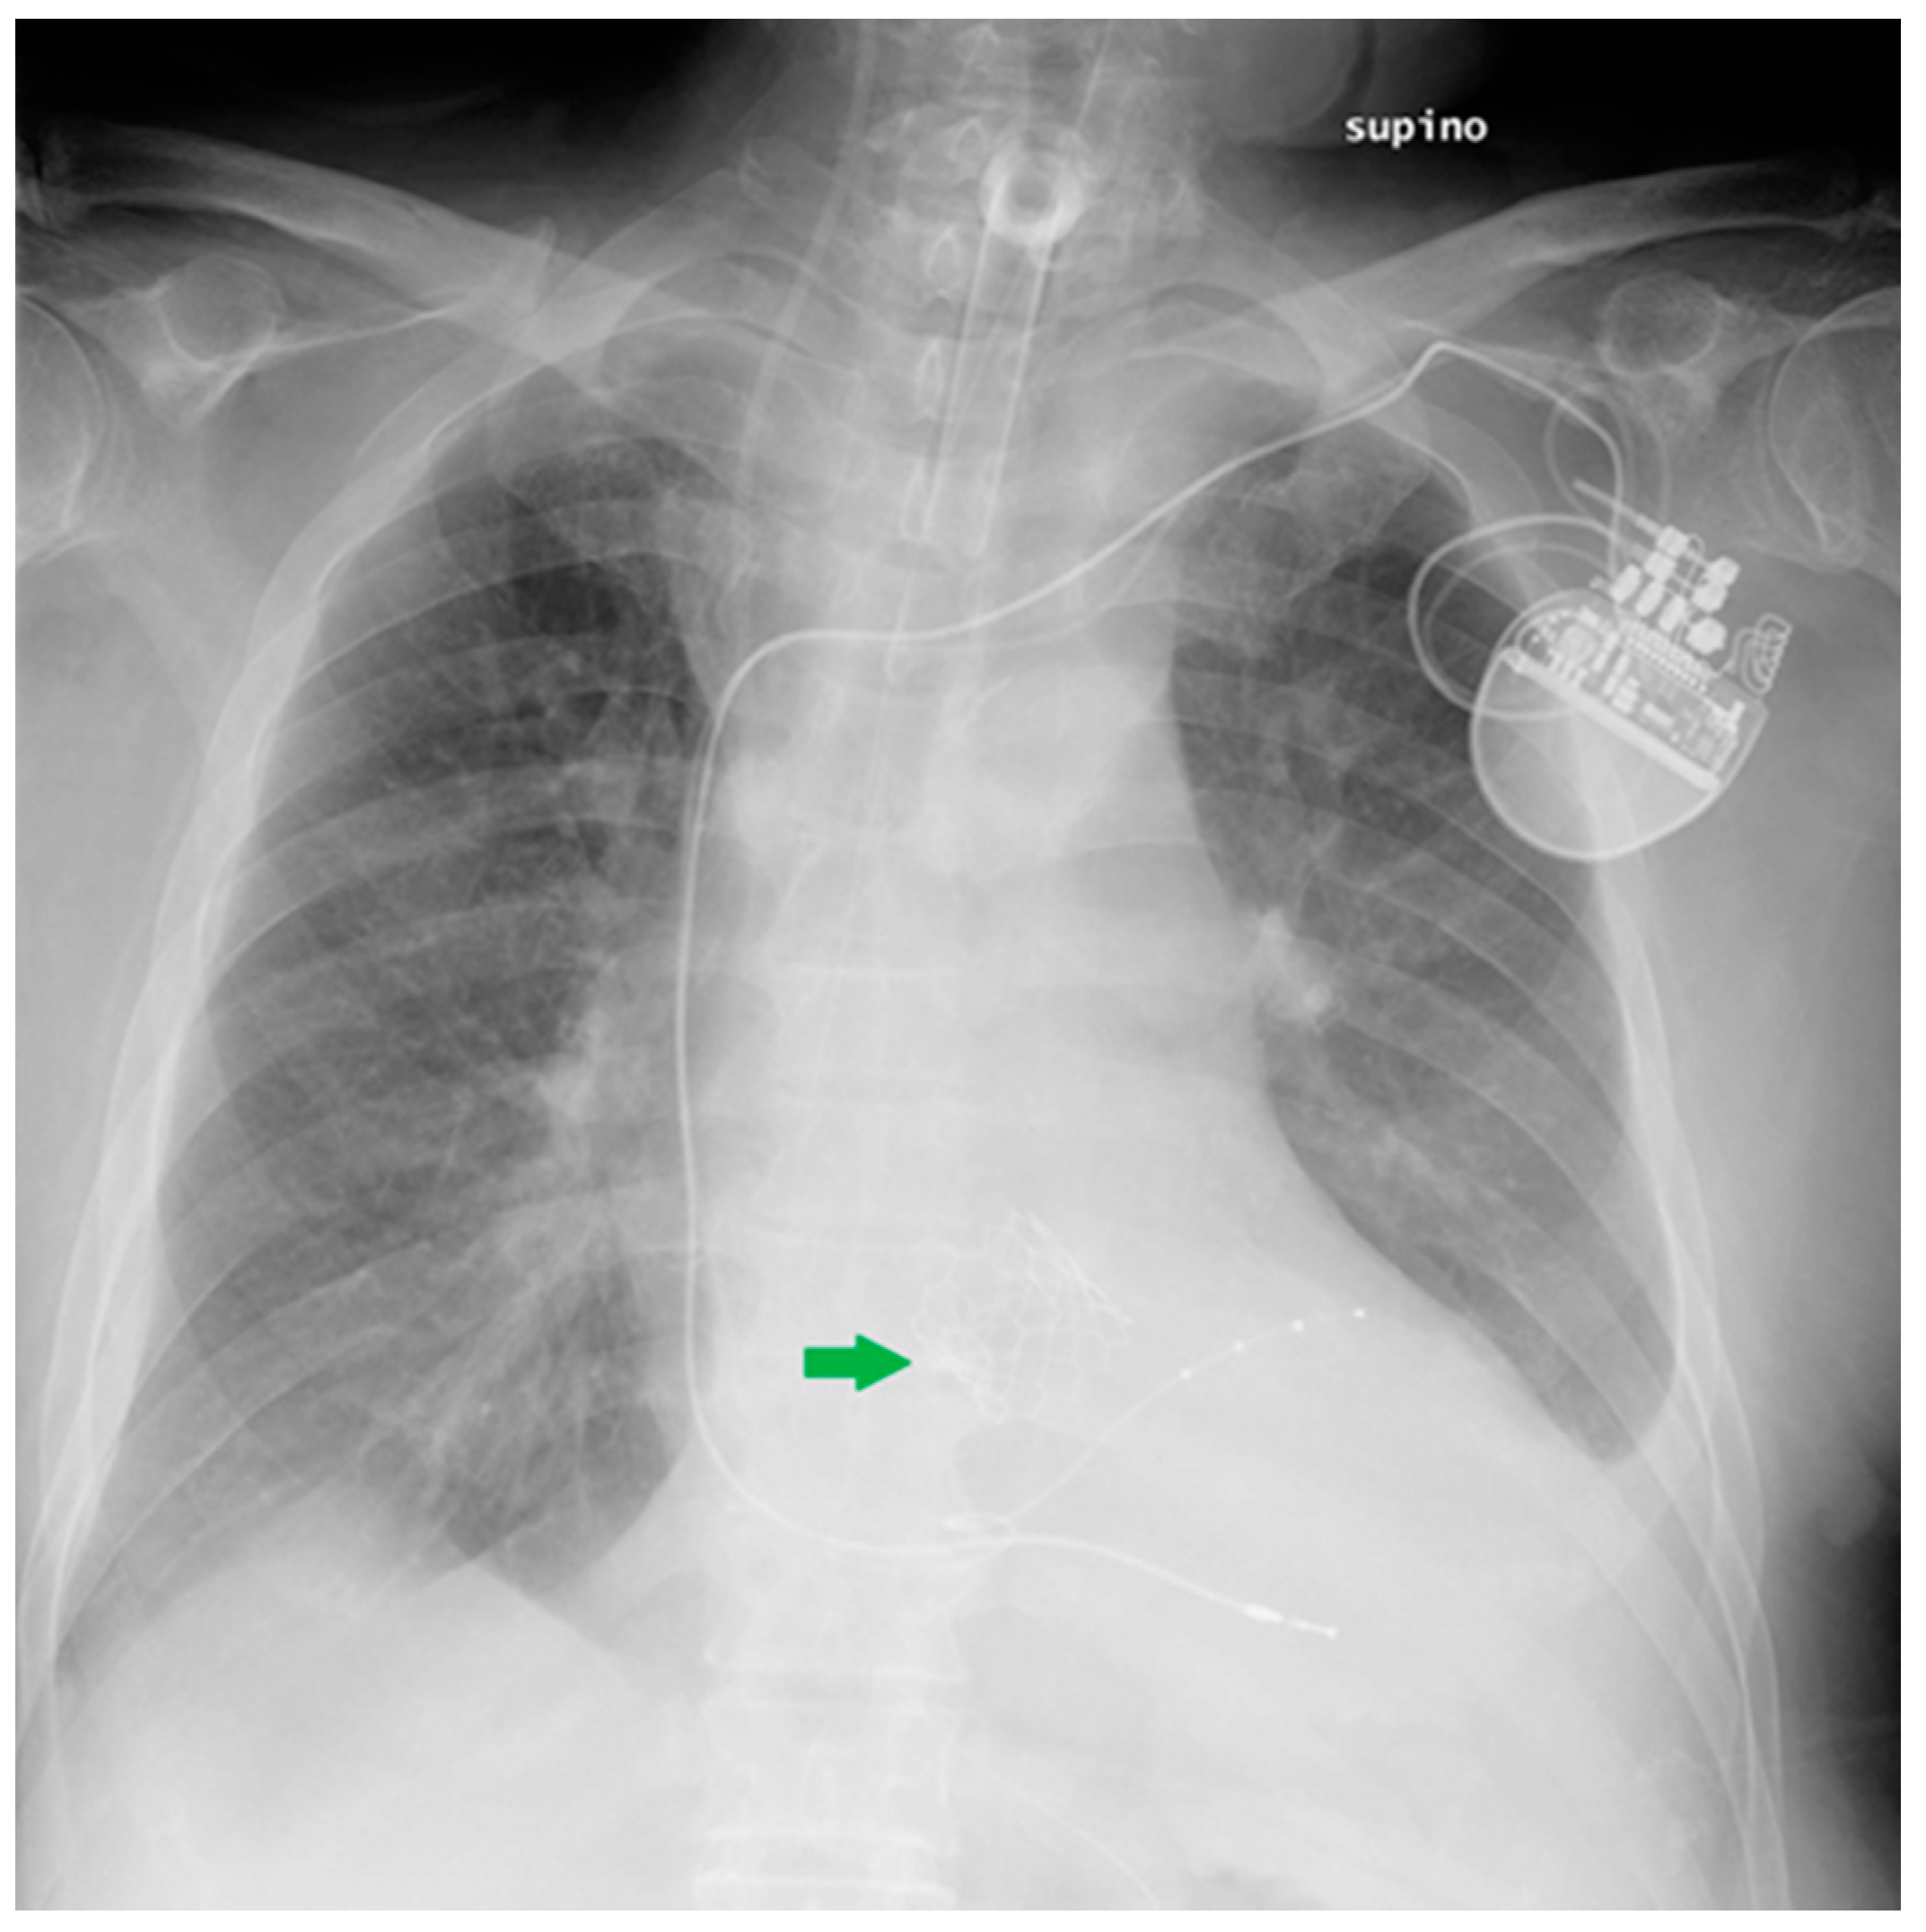

Figure 18.

This CXR shows the result of a transcatheter aortic valve implantation (TAVI) (green arrow). The radiogram also includes a PM, a tracheostomy tube and a right jugular CVC.